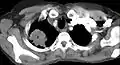

Chest X-ray showing a Pancoast tumor (labeled as P, non-small cell lung carcinoma, right lung), from a 47-year-old female smoker.

Diagnosis of a Pancoast tumor can be difficult in the early stages to the similarity of its symptoms with other conditions such as arthritis, with shoulder pain being one of the only symptoms that might indicate further imaging for a patient.[14] Though a chest x-ray is a good screening test and might be the first mode of imaging used, they are not easily seen during the early stages of the disease due to their size and location in the chest.[15]

Following the initial imaging, a CT scan or MRI is preferred since both can provide more details and information such as size, lymph node involvement and other areas of invasion, such as vascular involvement.[15][10]